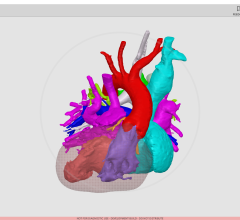

November 27, 2017 — At the 103rd Scientific Assembly and Annual Meeting of the Radiological Society of North America (RSNA), Siemens Healthineers debuted GOKnee3D, a magnetic resonance imaging (MRI) application that drastically shortens the time required to perform comprehensive diagnostic exams of the knee. Currently, a typical knee examination can be roughly 20 minutes. GOKnee3D enables a push-button, high-resolution diagnostic 3-D knee exam in just 10 minutes. The acquisition of high-resolution isotropic 3-D images subsequently allows flexible evaluation of the images in all possible planes, including double oblique and curved planar. Increasing MRI efficiency in this manner is especially important because knee examinations are the third most common type of MRI examination, accounting for 11 percent of all scans.

The volume acquisition of GOKnee3D is based on a CAIPIRINHA SPACE protocol, which enables higher scan speeds and optimal image reconstruction with better signal quality than in previous technologies. Supported by dedicated, high-channel knee coils as well as automated field-of-view adaptation based on machine learning and artificial intelligence, the MR scanner acquires the volume data of the knee joint at the touch of a button.

To develop and clinically validate the technique, Siemens Healthineers collaborated with Johns Hopkins University in Baltimore. “GOKnee3D enables comprehensive evaluation of internal derangement to the knee,” said Jan Fritz, M.D., assistant professor of radiology and radiological sciences at the Johns Hopkins University School of Medicine. “The fully automated CAIPIRINHA SPACE protocol provides high-quality MR imaging in 10 minutes and ensures consistency of image quality and operational efficiency. The high spatial resolution isotropic data sets help to visualize abnormalities with high accuracy, enable reformations of virtually any imaging plane, and create high-quality 3-D-rendered MR images.”